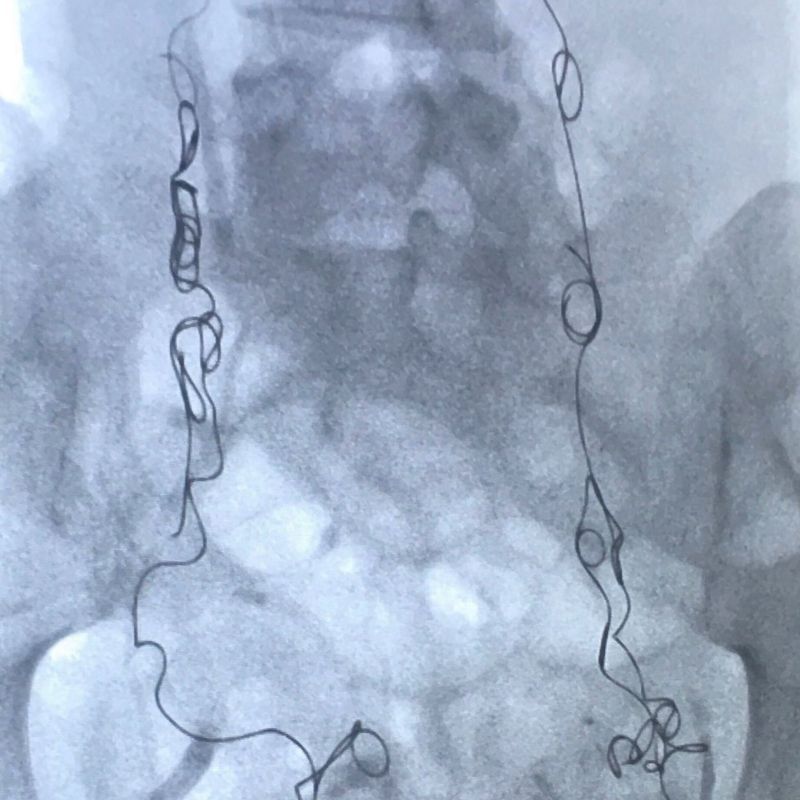

Es martes 14 de agosto de 2018 y estoy sedada, acostada en una mesa de operaciones, mientras me insertan espirales de metal en las venas ováricas y pélvicas a través de un catéter en el cuello.

No hay garantía de que el procedimiento, conocido como embolización venosa, funcione.

Pero me han dicho que en aproximadamente el 80% de los casos logra reducir o eliminar los síntomas por completo, por eso es mi mejor esperanza después de meses de dolor.

Él confirmó que tenía congestión pélvica en las venas ováricas izquierda y derecha, y en las ramas de otra vena de la pelvis, la vena ilíaca.

La embolización que me hicieron en agosto de 2018 bloqueó mis venas congestionadas con espirales de metal para que ya no pudieran llenarse de sangre, agrandarse y causarme dolor.